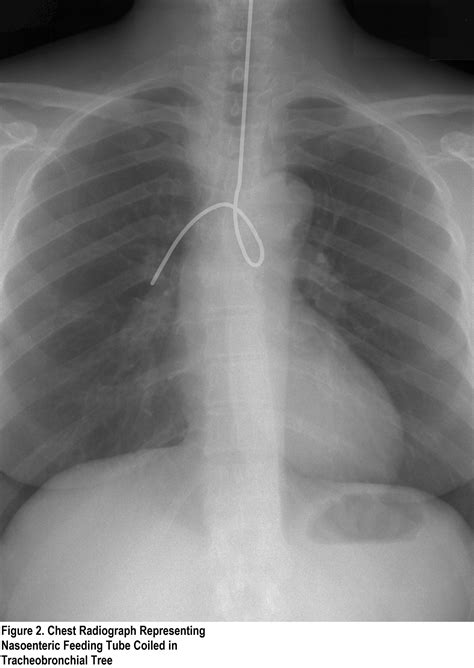

Complications of Ng Tube Insertion

While Ng tube insertion is generally safe, it can be associated with several complications:

• Esophageal Perforation: Although rare, the tube can perforate the esophagus, leading to serious complications.

• Aspiration: There is a risk of aspirating stomach contents into the lungs, which can cause pneumonia.